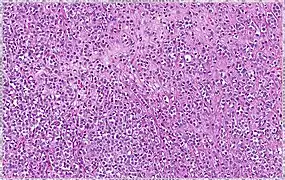

| Solid | 10% | Sheets of classical-appearing cells with little intervening stroma | |

Invasive lobular carcinoma demonstrating a predominantly lobular growth pattern.